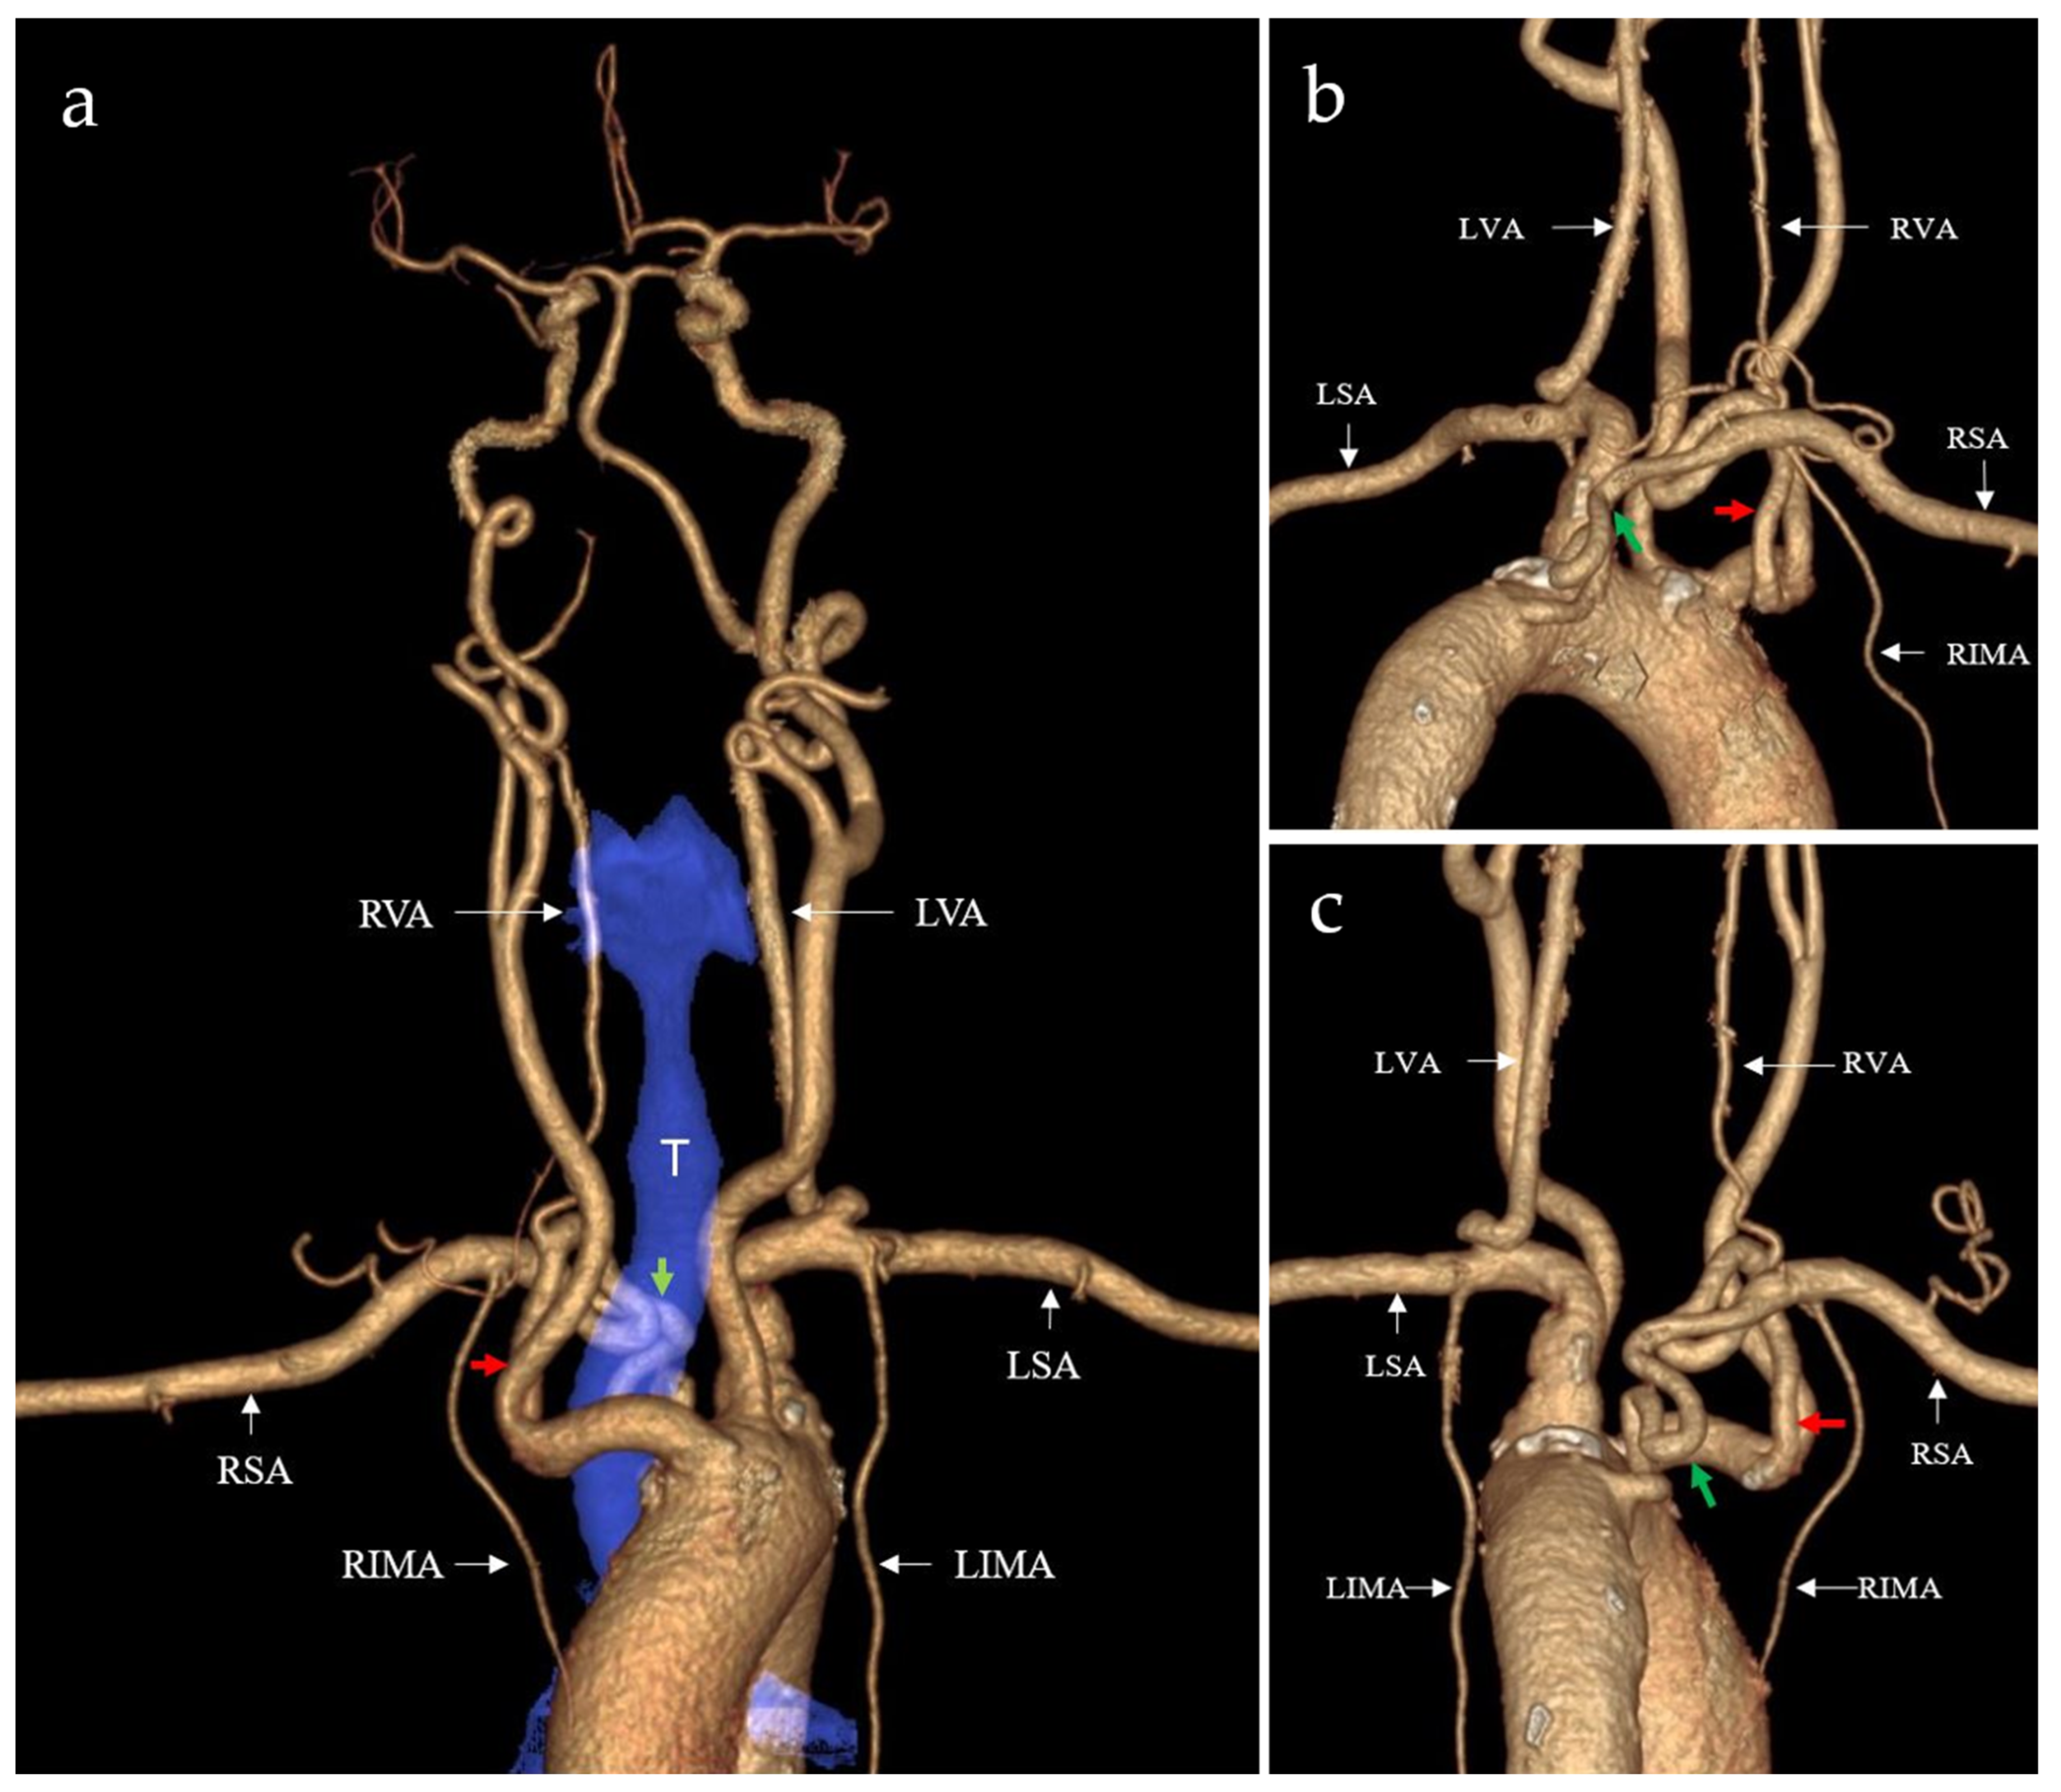

2. Case Presentation